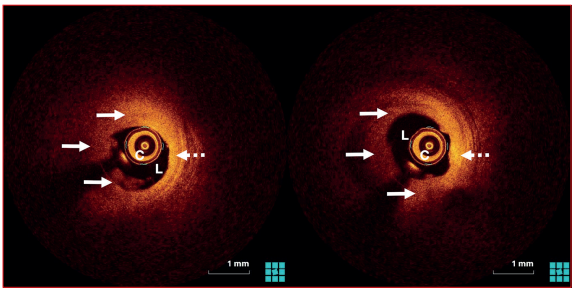

Al quinto día se realizó nueva CACG que constató estenosis residual leve (figura 3) y OCT que observó una reducción considerable de la carga trombótica, con una placa aterosclerótica subyacente que no determinaba una estenosis significativa, y sobre la cual se identificó, como proceso fisiopatológico causante del evento, la disrupción intimal (figura 4). En ausencia de estenosis significativa se decidió no implantar stent y continuar con tratamiento médico con doble antiagregación y anticoagulación.

En el caso que se presenta, la OCT inicial observó una alta carga de trombo rojo endoluminal, que impidió la visualización de la placa aterosclerótica subyacente. El trombo se visualiza como una masa irregular que protruye dentro de la luz, ya sea unida a la pared, o que flota en su interior, pueden diferenciarse los trombos blancos (alta reflectividad y baja atenuación) de los trombos rojos (baja reflectividad y alta atenuación). La OCT de control al quinto día del evento agudo observó una disminución significativa de la carga trombótica, que permitió evaluar las paredes del vaso en su totalidad, determinar la severidad de la estenosis residual e identificar la causa del SCA, siendo en este caso la ruptura de placa (figura 4). Esta constituye la causa del 64,3% de los SCA y se visualiza como una zona de disrupción de la cápsula fibrosa que recubre un core lipídico vacío3,4. Otros mecanismos causantes de SCA que se pueden distinguir mediante OCT son: la erosión de placa, que se da entre el 26,8 y 33% de los casos y se caracteriza por presentar una superficie irregular sin discontinuidad de la capa fibrosa, con o sin trombo asociado; el nódulo calcificado, que se caracteriza por su elevado contenido de calcio y se encuentra en el 8% de los casos; y la disección espontánea, que se observa como una imagen de doble luz y se encuentra entre el 0,9 y 2,1% de los casos3,4.

La OCT también permite realizar una evaluación detallada de la morfología y la estructura de la placa aterosclerótica y de sus componentes, características que reflejan su vulnerabilidad y la probabilidad de presentar una complicación y, en consecuencia, un evento coronario agudo. Se pueden distinguir tres tipos principales de placas: las fibrosas, estructuras homogéneas de alta reflectividad; las fibrocalcificadas, estructuras de baja reflectividad con bordes bien delimitados; y las lipídicas, de baja reflectividad con bordes difusos. En la (figura 2) se puede observar sobre el sector de arteria “visible” (no tapizado por trombo) una placa aterosclerótica que, por sus características, podemos definir como fibrosa (de forma homogénea y elevada reflectividad).